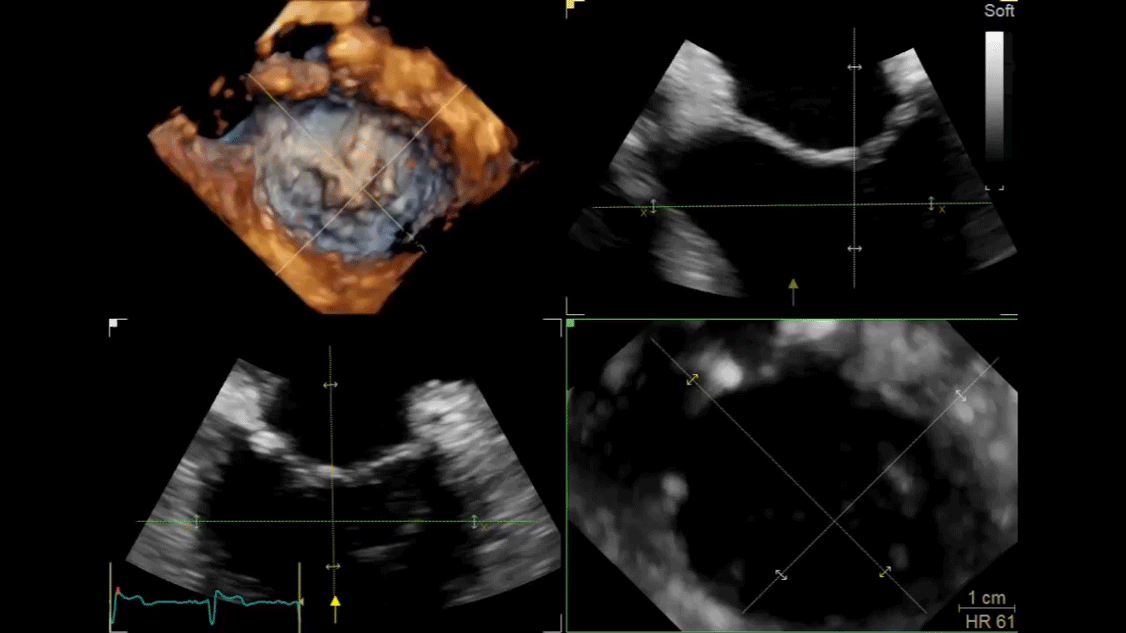

Ultra-high single-beat volume rates With TEE procedures growing, so is the need to find ways to achieve the benefits of 4D imaging without compromising productivity. VmaxTM enabled by cSound™ 2.0 offers ultra-high 4D volume rates acquired in single beat acquisition with no loss of image quality. Elimination of ECG gated multibeat/stitching acquisition provides enhanced overview of structures and function in cases with high and/or irregular heart rhythm - which potentially reduces interventional procedure time and improves patient outcomes.

4D TEE color imaging with Vmax

4D Auto MVQ*

4D Auto AVQ*